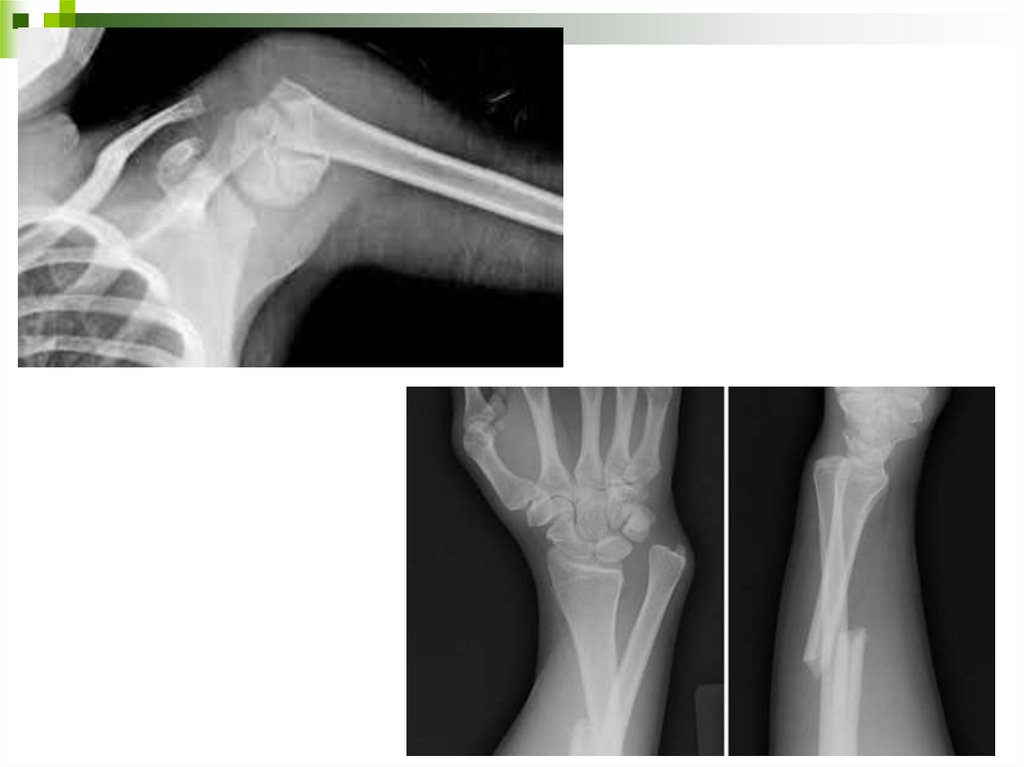

9.

10.

11. Диагностика вывихов

Клинические признаки:

- боль;

- деформация сустава;

- изменение внешних ориентиров сустава;

- отсутствие активных движений в суставе;

- при пассивных движениях симптом пружинящего

сопротивления (ощущение упругого сопротивления

движению, а при прекращении усилия сегмент

конечности возвращается в прежнее положение)

- при пальпации головка кости пальпируется в не типичном

месте.